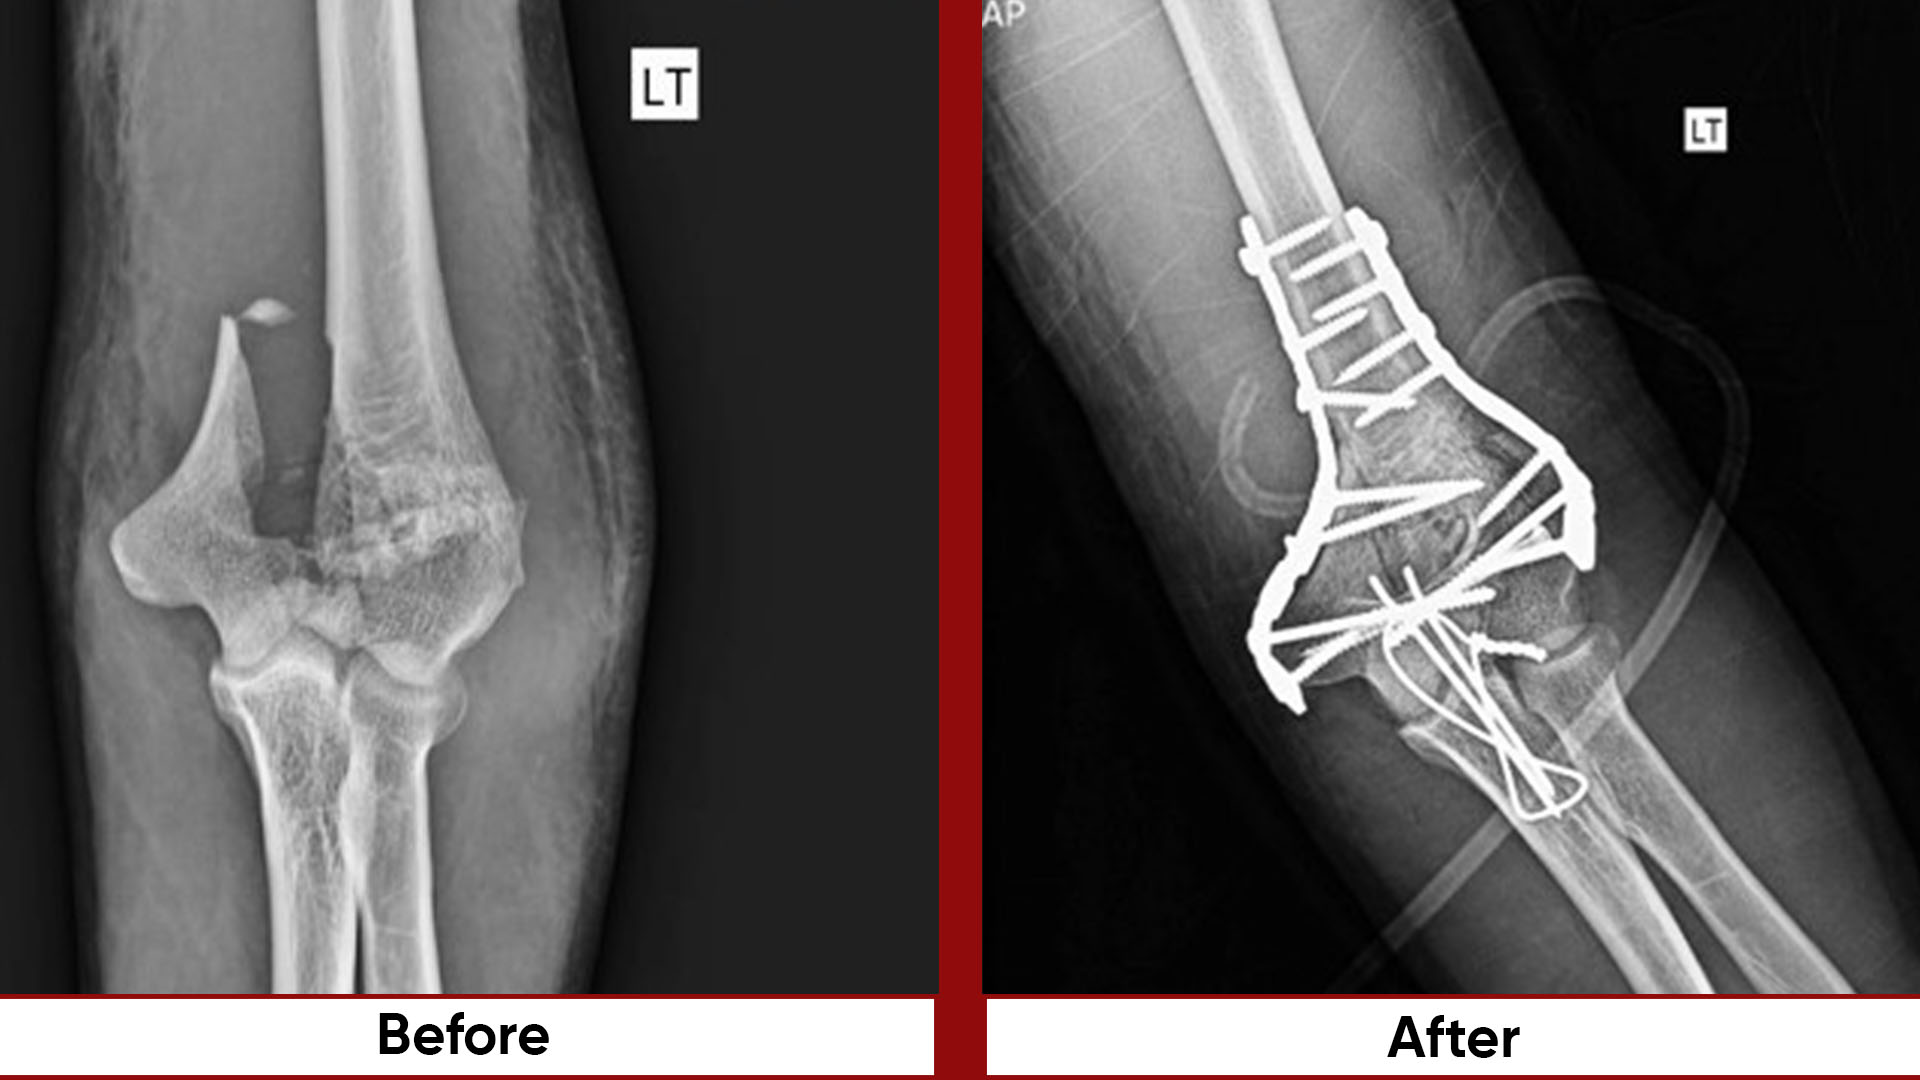

• Fracture Management (simple and complex trauma)

• Arthroscopic Surgeries (Knee & Shoulder)

• Joint Preservation Surgery

• Deformity Correction (limb lengthening, bowlegs, knock knees)

• Osteotomies (bone realignment surgeries)

• Pelvic & Acetabular Fracture Fixation